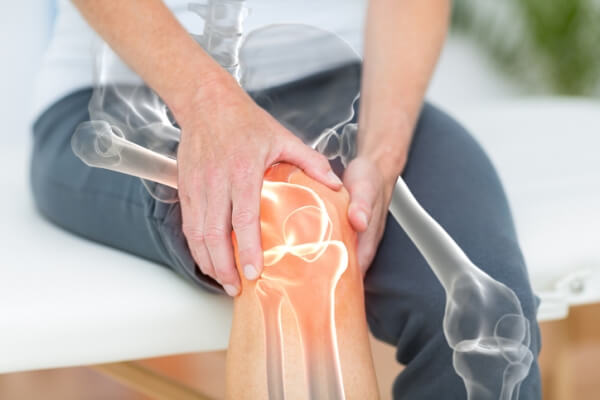

류마티스 관절염이란 우리 체내 면역체계에 이상이 생겨 관절 내에 염증이 생겨나게되고, 관절이 점차 파괴되는 증상이 지속되어 턱, 척추, 손, 발, 손목, 발목, 무릎 등의 관절에 영향을 미치는 만성질환을 말해요. 또한, 눈, 피부, 폐, 혈관 등에도 손상을 줄 수 있답니다. 퇴행성 관절염은 노화가 일어나면서 자연스럽게 관절에도 문제가 생기는 상태라고 볼 수 있으며, 류마티스 관절염은 노화와는 무관하게 자가 면역체계의 문제로 인하여 관절염이 생기는 상태입니다.

류마티스 관절염은 갑자기 시작되어 또한, 다수의 관절에 염증이 발생할수 있고, 보다 빈번히 점진적으로 시작되고 상이한 관절에 영향을 미치게 되어요. 보통 염증은 대칭적으로 인체 양쪽의 관절들이 일정하게 영향을 받으며, 류마티스 관절염은 어떠한 관절에도 영향을 미치지만 가장 흔한곳은 손, 손목, 손가락, 발, 발가락 또는 무릎, 어깨, 팔꿈치, 발목, 고관절 입니다.

류마티스 관절염은 혈관 염증, 혈관염을 유발하며 혈관염이 조직으로서의 혈액공급을 낮춰주고 신경 손상 그리고 다리 궤양을 야기할 수 있고, 폐를 덮는 막 즉 흉막 그리고 심장 주변의 주머니 그리고 폐 혹은 심장 염증과 흉통 그리고 숨가쁨을 초래할수 있습니다. 일부 사람들은 종창성 림프절 펠티 증후군 쇼그렌 증후군 눈의 흰자위 연화 염증으로써 인한 충혈 또는 자극된 눈을 보이기도 합니다. 또한, 류마티스 관절염은 목에 영향력을 끼쳐 뼈를 불안정하게 만들고 뼈가 척수에 압력을 가하는 위험이 증가할 수 있습니다.